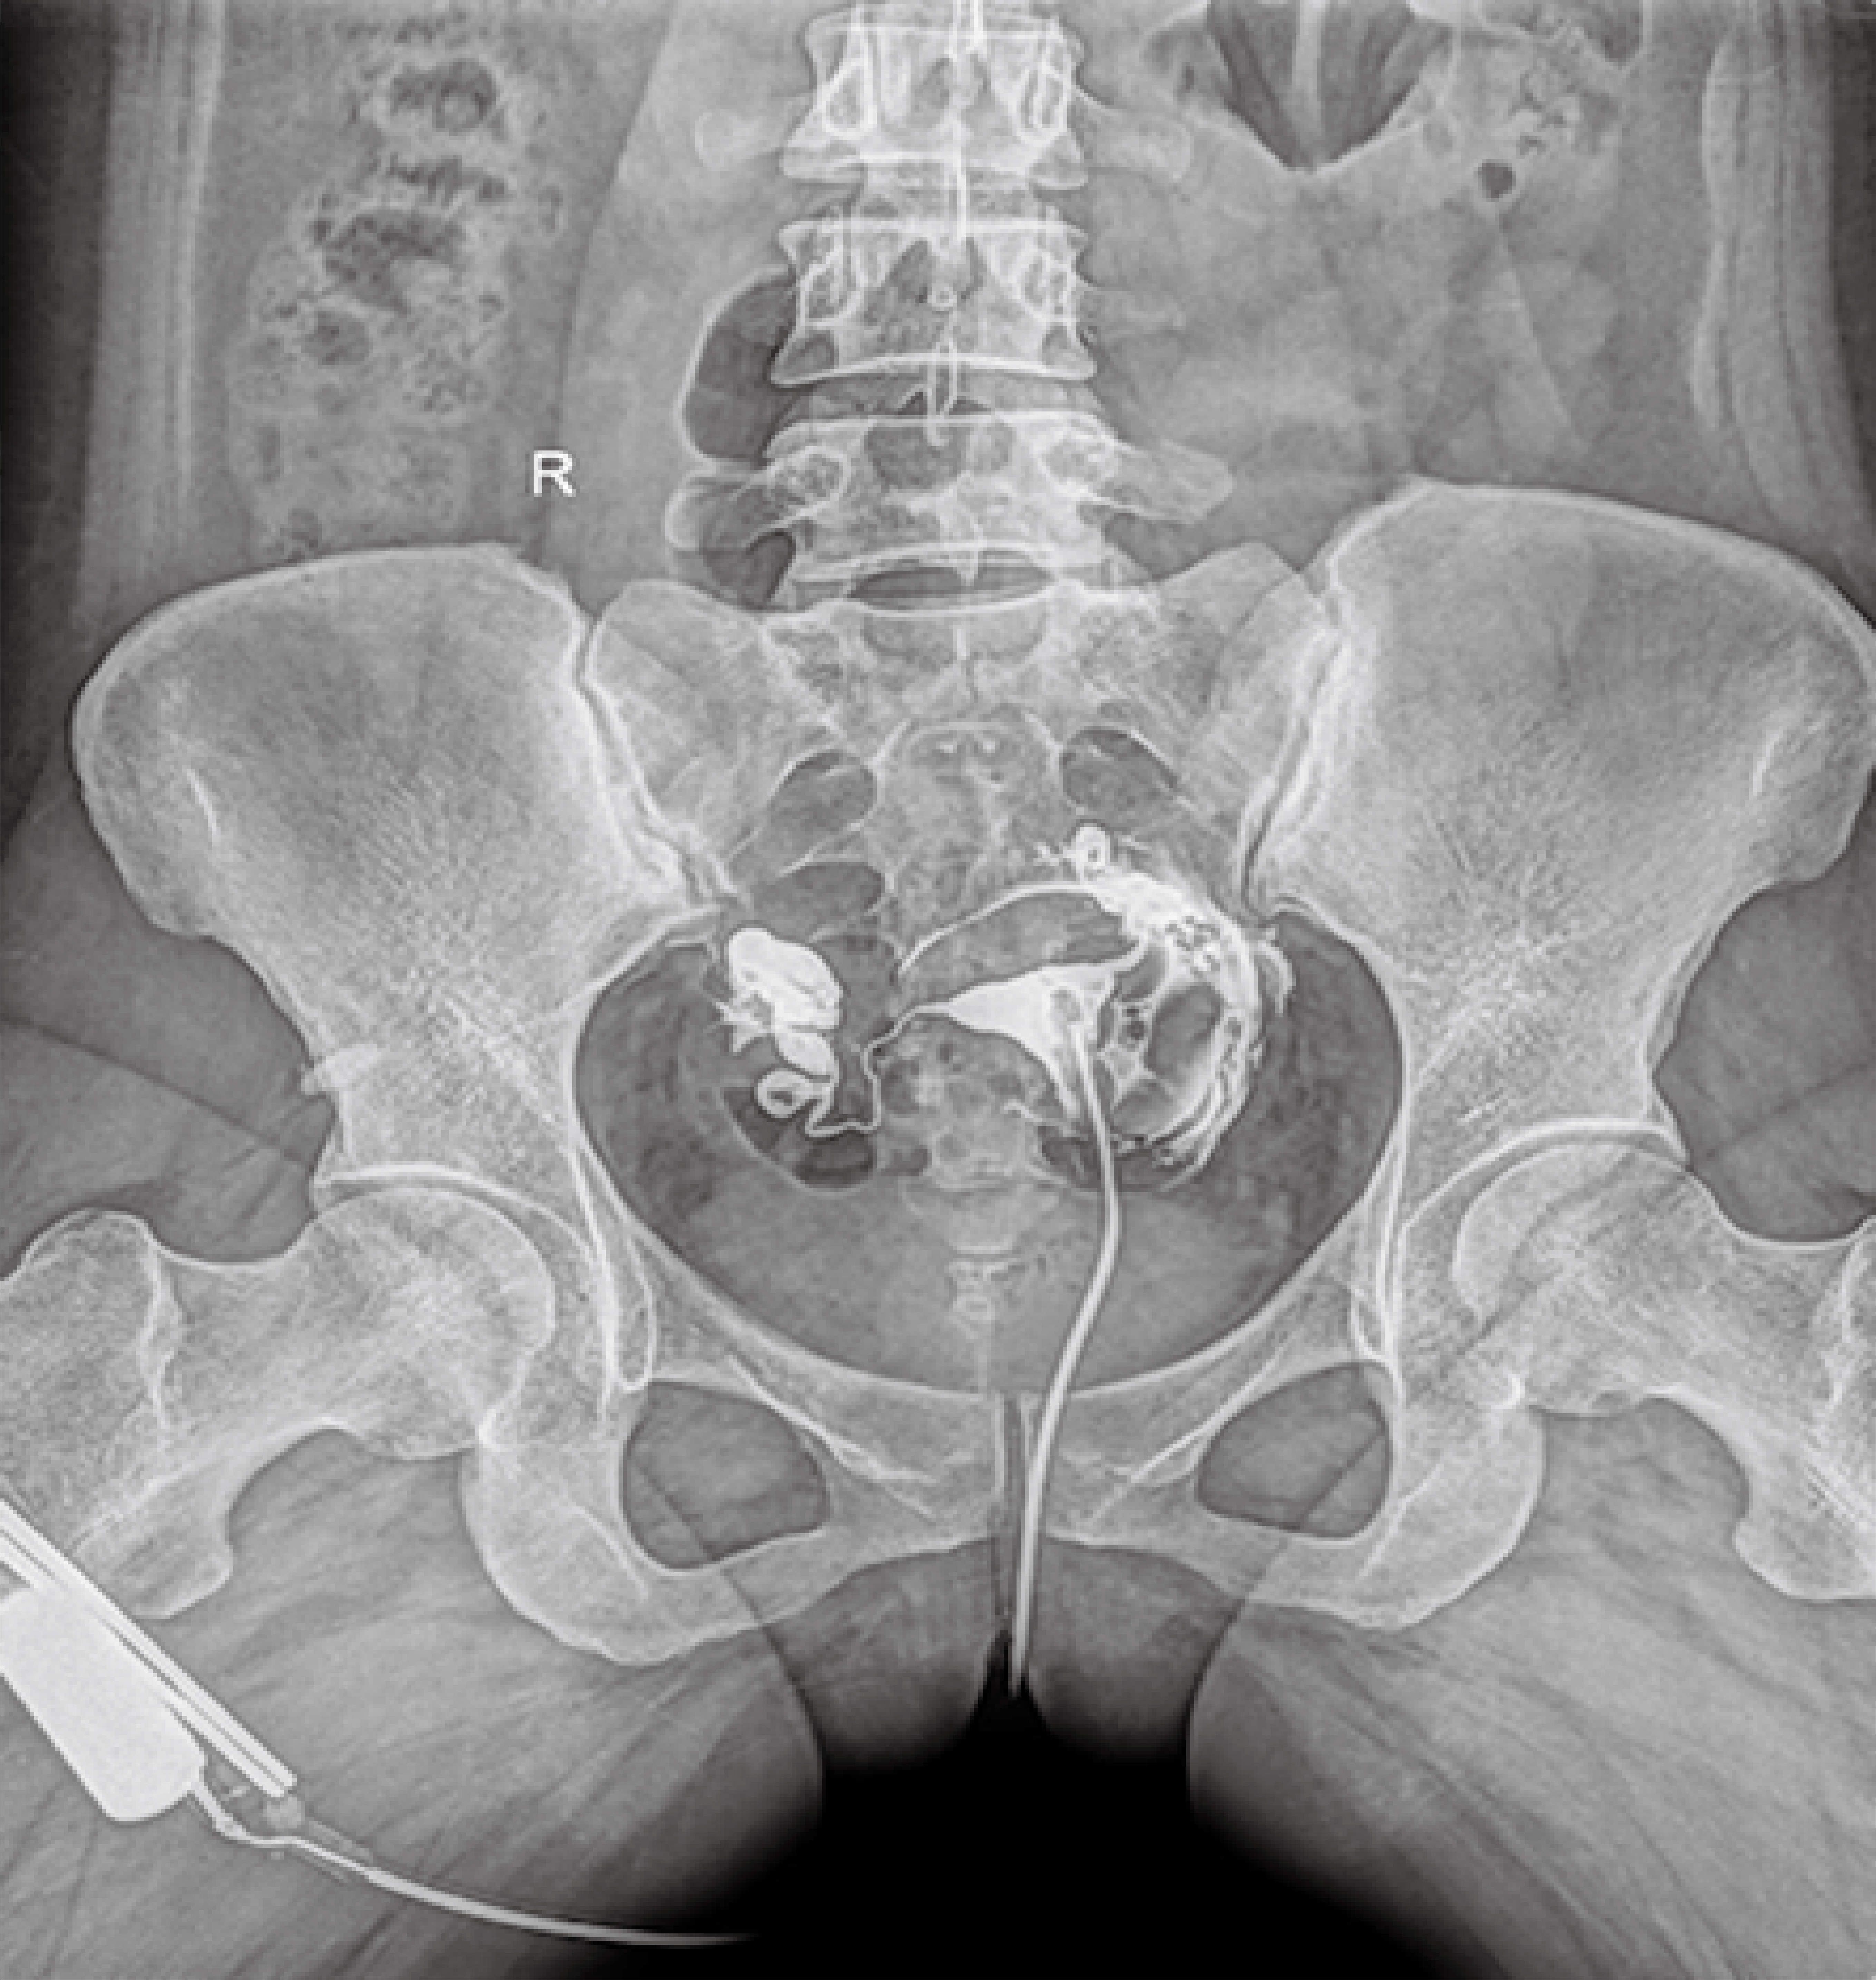

普利德醫(yī)療自主研發(fā)的新一代數(shù)字化X線透視攝影系統(tǒng),可應(yīng)用于DR攝影、數(shù)字透視、數(shù)字造影以及可視化精準(zhǔn)DR拍片等多種臨床X線檢查領(lǐng)域。

點(diǎn)片裝置移動(dòng)范圍大,無(wú)需患者移動(dòng)就能完成全身各部位的檢查;

床面橫向移動(dòng),輕松實(shí)現(xiàn)機(jī)動(dòng)人不動(dòng)。